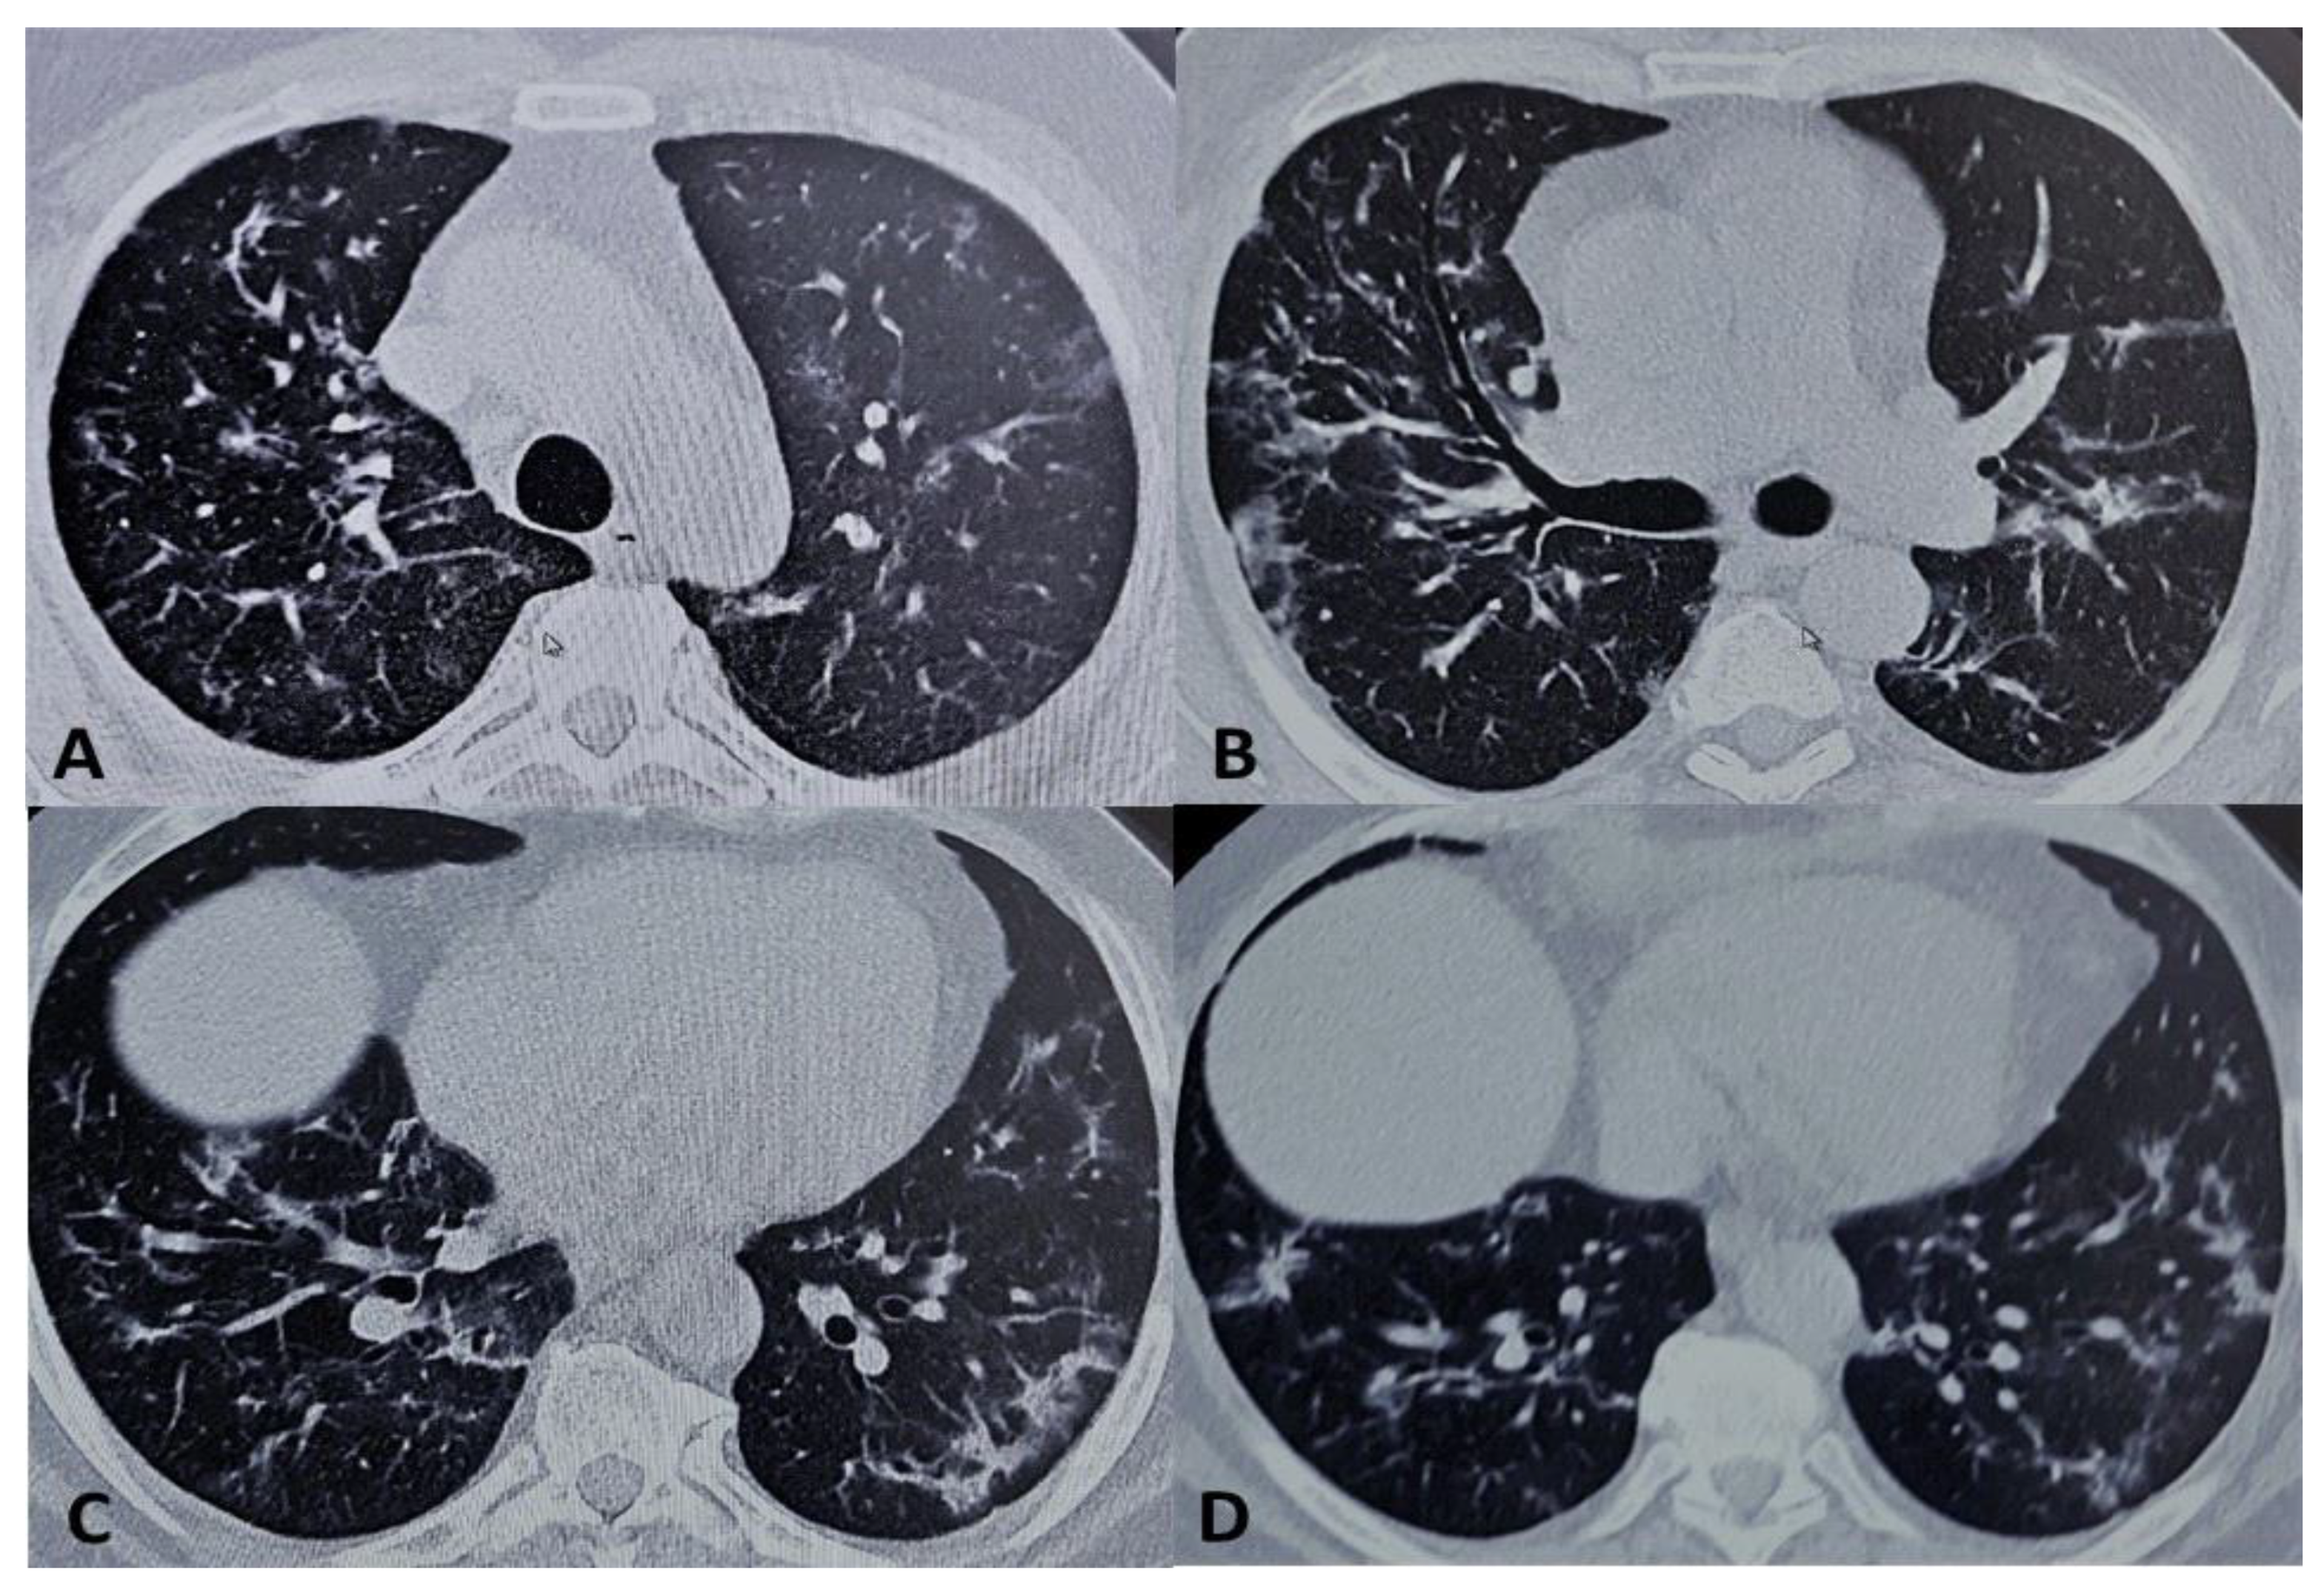

- Cellina, M.; Orsi, M.; Bombaci, F.; Sala, M.; Marino, P.; Oliva, G. Favorable Changes of CT Findings in a Patient with COVID-19 Pneumonia after Treatment with Tocilizumab. Diagn. Interv. Imaging 2020, 101, 323–324. [Google Scholar] [CrossRef] [PubMed]